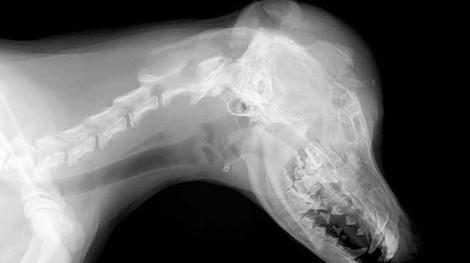

Η ανθρώπινη κτηνωδία δεν έχει όρια… Ιδιοκτήτης ταβέρνας σκότωσε – μπροστά στα μάτια των πελατών του – ένα αδέσποτο σκυλάκι, ηλικίας τριών μηνών, χτυπώντας το μανιωδώς με μία καρέκλα το βράδυ της Πέμπτης στα Νέα Στύρα στη νότια Εύβοια.